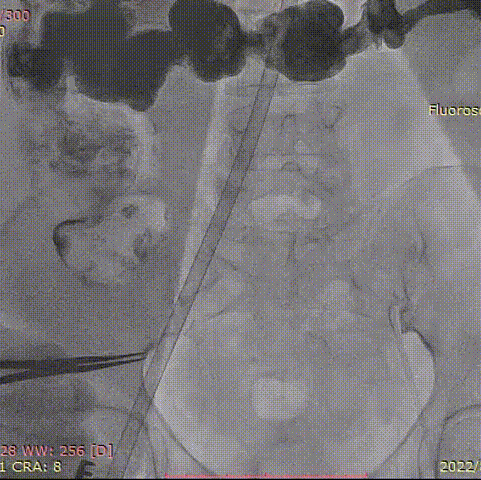

手术过程

20mm球囊预扩张:

球囊有明显腰征,无漏。

第一次定位释放:

瓣膜定位

瓣膜微释放

释放至工作位

超声明确瓣膜位置

完全回收,第二次定位释放:

术后造影:

大鞘撤出外周血管,造影

瓣膜释放后超声评估:

术中,心外体外循环科郑军医师全程待命。彩超室张俊鹏老师全程跟台,术后行超声探查未见瓣周漏,血压改善。